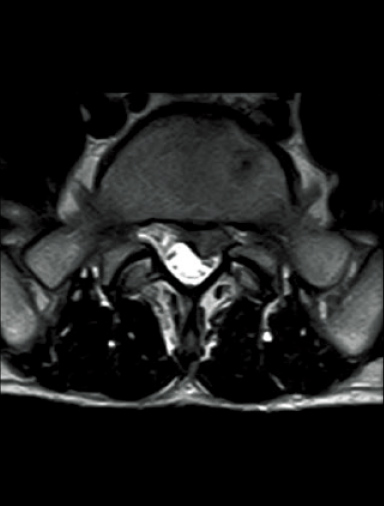

FatSep-T2*WI

FatSep-T2WI